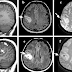

61 studi scientifici sulla Trombosi Venosa Cerebrale dopo il vaççino çovid

›

TROMBOSI VENOSA CEREBRALE Un tipo di ictus in cui i canali venosi del cervello vengono trombosati, causando infarto cerebrale nelle aree cor...